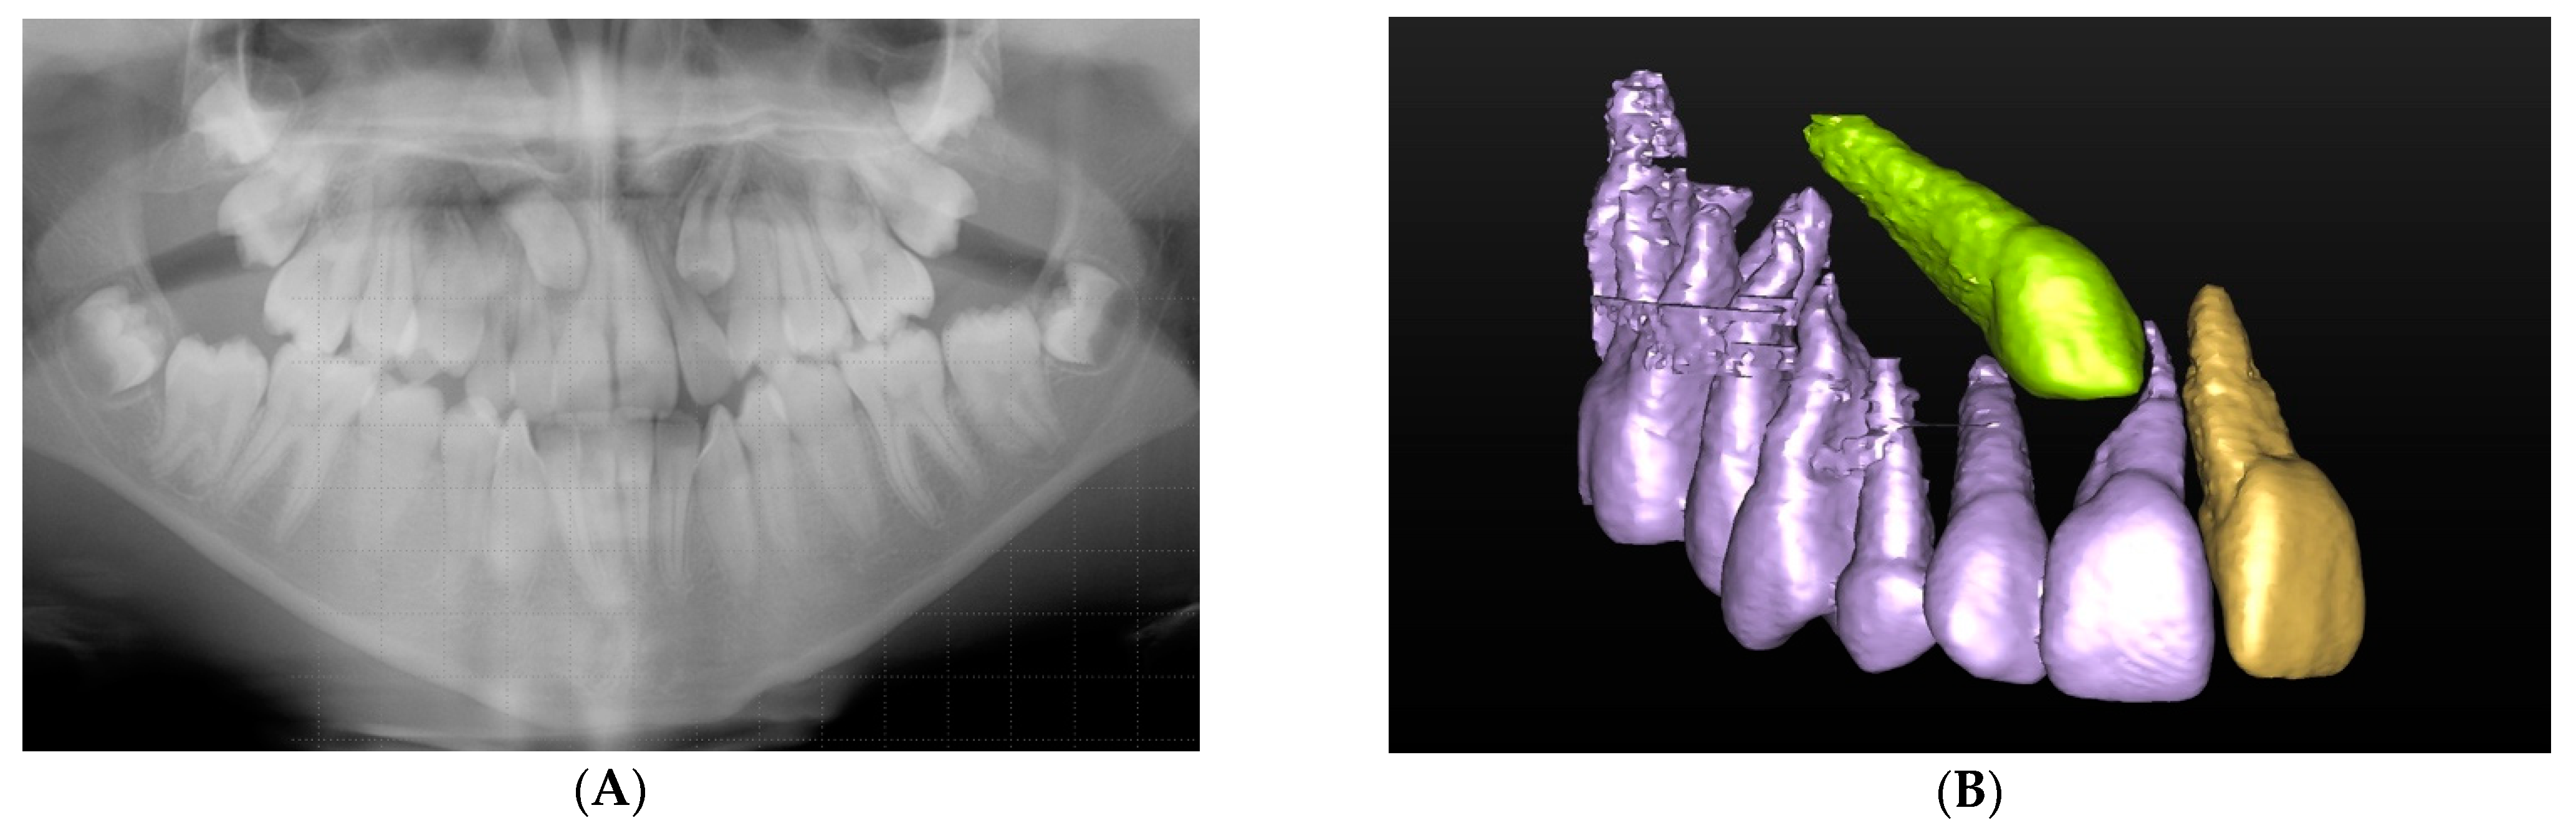

Figure 1 represents an impacted canine case that was referred for CBCT to assess localisation and the extent of root resorption after the panoramic radiographic revealed root resorption of the upper right central incisor. The provisional treatment plan, which suggested the surgical exposure of the upper right canine for orthodontic alignment into the upper right central incisor position, was altered following the acquisition of additional information from the CBCT. The CBCT revealed the exact inclination of the long axis of the canine, the extent and location of the root resorption of the upper right central incisor and of the upper right lateral incisor. Due to the unfavourable oblique position of the upper right canine, the treatment plan was revised for its surgical removal. The upper right central incisor was deemed poor prognosis due to the significant resorption visualised in the apical root third with pulpal involvement and was to be closely monitored alongside the upper right lateral incisor.

Figure 1.

(A) Panoramic radiograph showing bilateral ectopic and impacted canines. (B) Three-dimensional (3D) segmented reconstruction showing the position of the upper right ectopic canine localisation and associated resorption of the upper right central incisor (©DentsplySirona-Simplant® Pro).